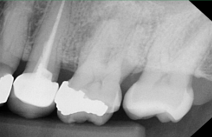

CBCT Scans provide a 3D dental image, while traditional X-rays are only a 2-dimensional picture of the mouth. This means that with traditional X-rays alone, it is very difficult to diagnose non-painful lesions like dental abscesses that are within the jaw bone.

Here are some examples of photos of bone lesions

Patient “A ”Xray of a root canal tooth #14 CBCT Scan of same tooth #14, notice the lesion on the bone at the tip of the left root Notice root canal #13 on xrays CBCT Scan on same tooth #13, there is a lesion at the tip of the root causing sinus membrane inflammation. Patient “C” xray tooth #14 Patient “C” CBCT Scan tooth #14, bone lesion affects both roots. Upland Lighthouse Dentistry, a renowned family dentist in Upland, offers cone beam CBCT scan technology for comprehensive dental care. Our expert dentist utilize this advanced 3D imaging technique to obtain precise details of dental structures, soft tissues, and nerve paths, enhancing our diagnostic accuracy and treatment planning. Contact Upland Lighthouse Dentistry today!